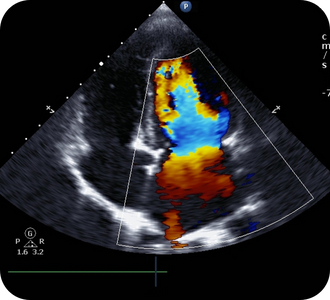

O ecocardiograma com Strain é uma técnica avançada que avalia de forma precisa a função do músculo cardíaco, identificando alterações sutis da contratilidade que muitas vezes não são visíveis no ecocardiograma convencional.

É especialmente indicado no acompanhamento de pacientes com hipertensão, cardiopatias, doenças valvares, cardiotoxicidade por quimioterapia e avaliação precoce de disfunção cardíaca.